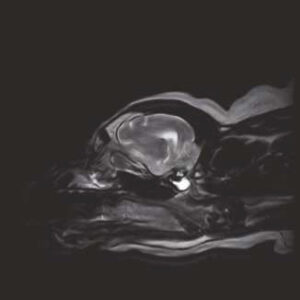

- Image Quality comparable to 1.5T MRI in the market

The PANION PRO comes with the double-pole open magnet design with a wide opening gap of 40 cm to accommodate large-sized animals on an efficient patient handling platform, the strongest gradient amplitude at 33mT/m and slew rate of 90 T/m/s, among all other open MRI systems, resulting in high spatial resolution of images in short scan time. The 6-direction patient table permits iso-centre imaging of all anatomical regions.

Clinical Images